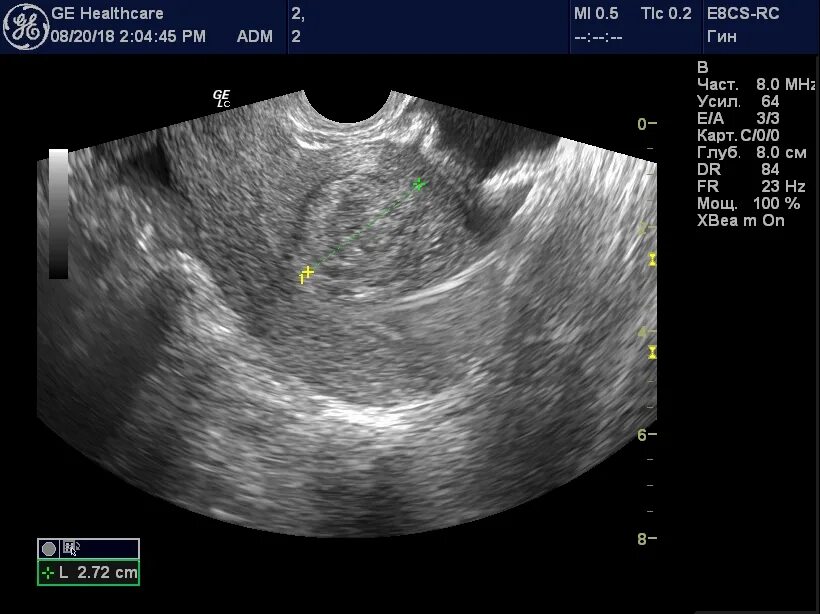

Как лечить миому матки без операции